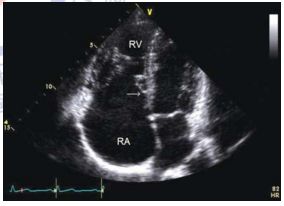

159.參考圖 A, B, C, 請問下列敘述何者錯誤?

(A) 此疾病早期 (early stage),還保有左心室收縮功能。 (B) 此疾病,左心室舒張末期壓力上升,影響左心房收縮血液至左心室,因此二尖瓣血 流 (mitral flow) 之 A 波通常變小。 (C) 此疾病,左心房壓力上升,影響肺靜脈血流 (pulmonary vein flow),造成肺靜脈血流 之流速在收縮期時 (S) 降低。 (D) 由於全面舒張期異常,因此,tissue Doppler 在二尖瓣環狀 (mitral annulus) 之 E’流 速通常小於 7 cm/sec。 (E) 此疾病主要是因為心包膜異常變厚,或是發炎,或是鈣化,而導致舒張期填充 (diastolic filling) 異常。